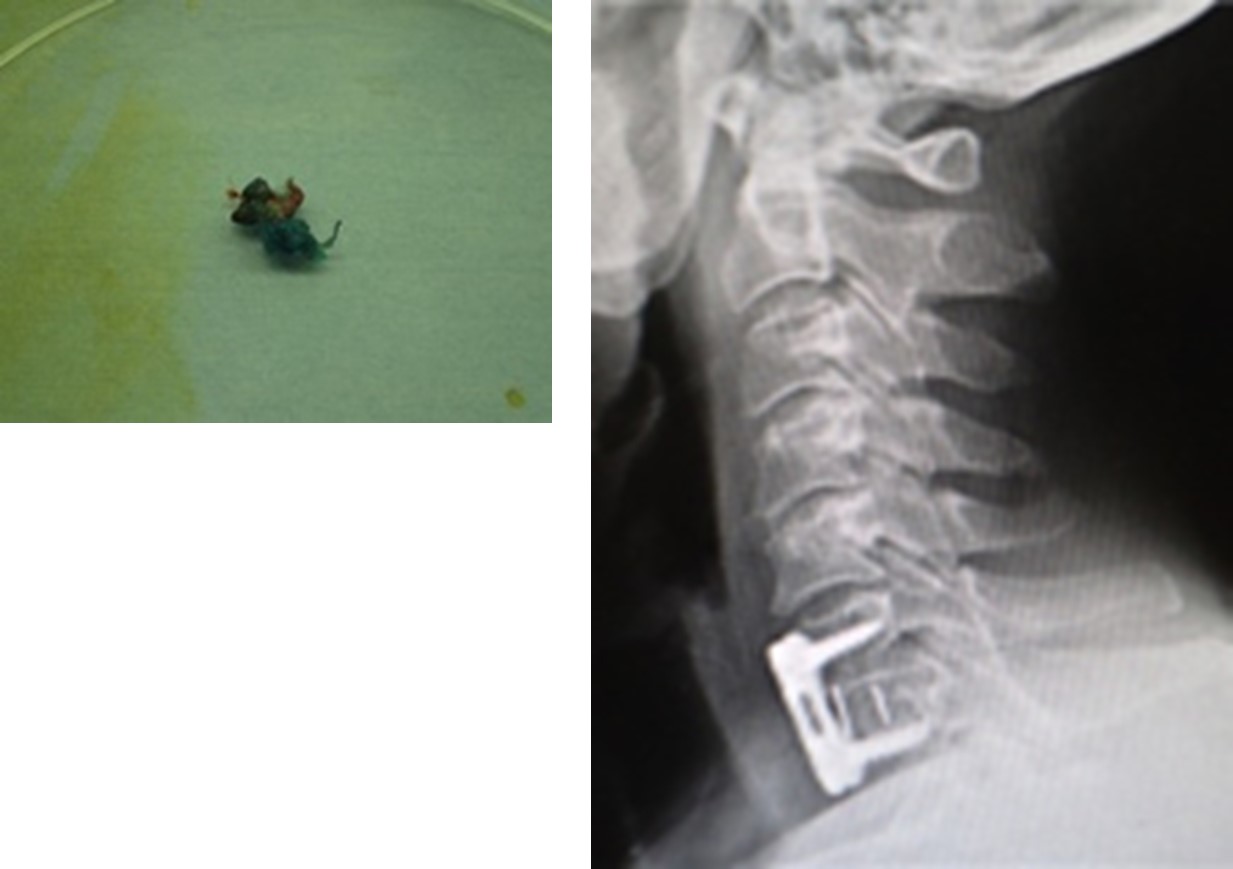

図(左)摘出した椎間板

(右)インプラントで上下の骨を固定しています